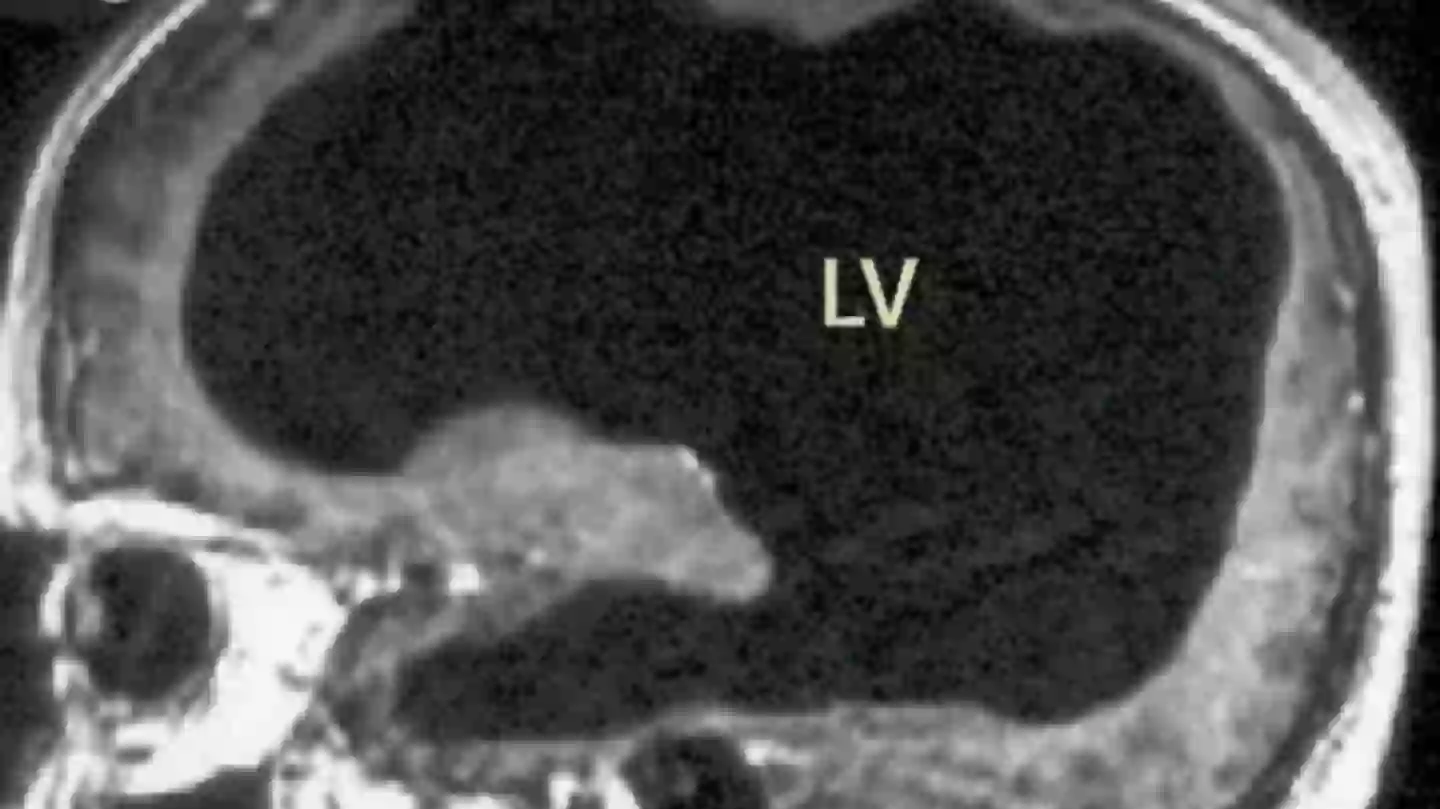

Following an MRI, the scans shown that most of the mans skull was filled with fluid, instead of brain tissue.

While it was initially thought that brain tissue had eroded, scientists now believe that it was compressed by the fluid.

The brain tissue was compressed into a thin outer layer along the edges of his skull, leaving 90 percent of the skill filled with fluid, instead of brain matter.

The scans left doctors baffled (The Lancet)